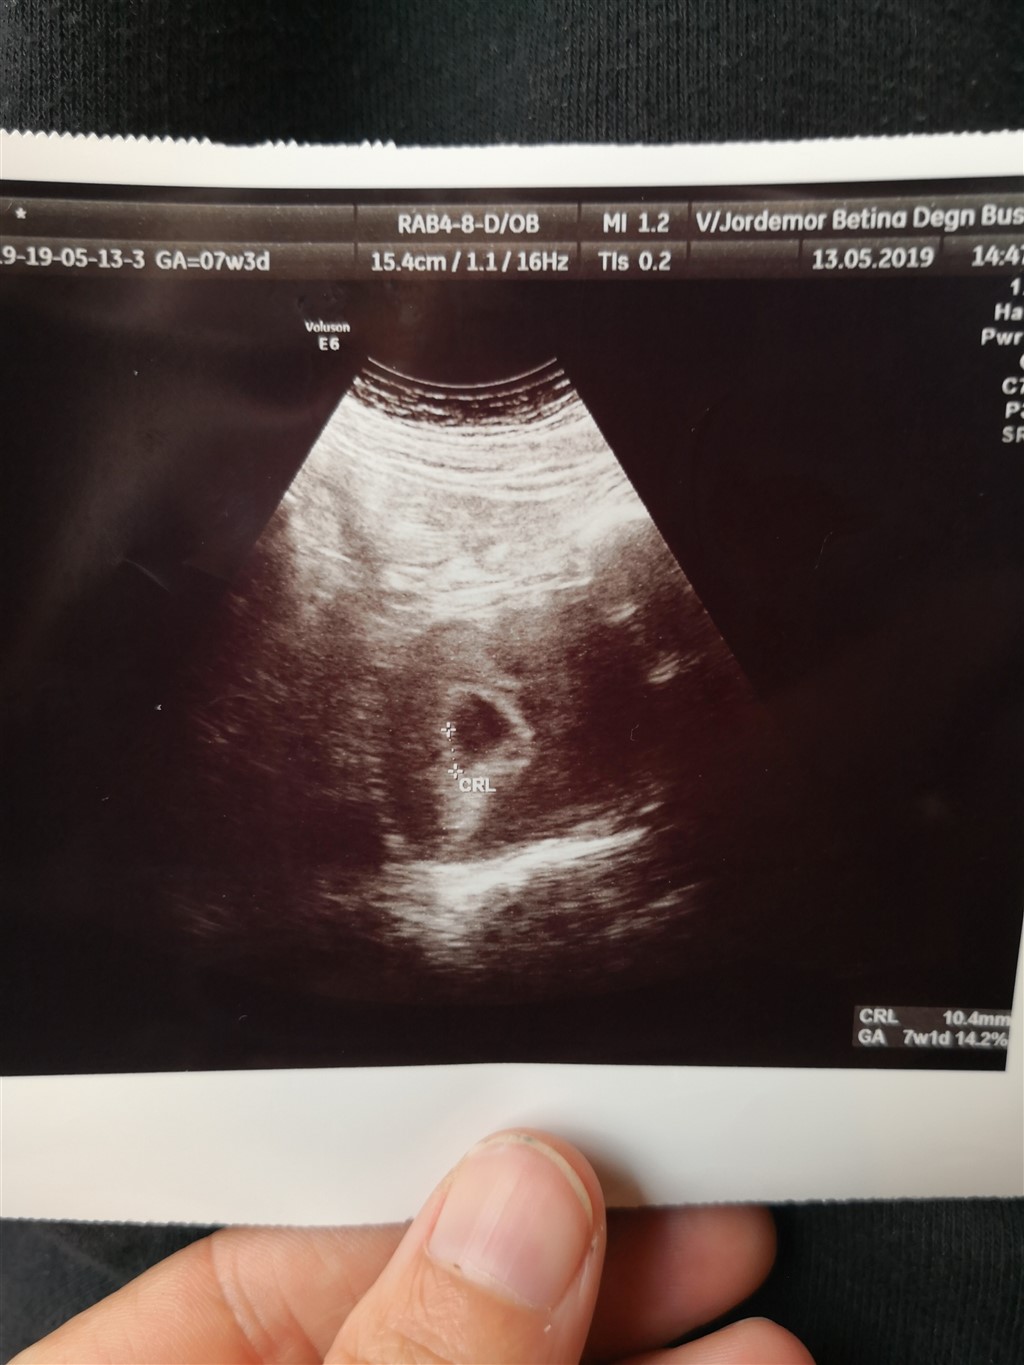

Vi valgte at købe en tidlig tryghedsscanning i dag for at være sikre på at der er liv.

de kunne godt se at der var noget og det der var, svarede meget godt til at jeg skulle være 7+3, men hun kunne ikke finde hjerteblink, sandsynligvis fordi den ligger helt op af livmodervæggen og fordi min livmoder så ud til at være bagoverbøjet. (hvilket undrer mig, da jeg ikke havde bagoverbøjet livmoder da jeg ventede min datter. ellers fik jeg bare aldrig besked om det)

Jeg skal til læge på torsdag og bliver sendt videre til scanning derfra.